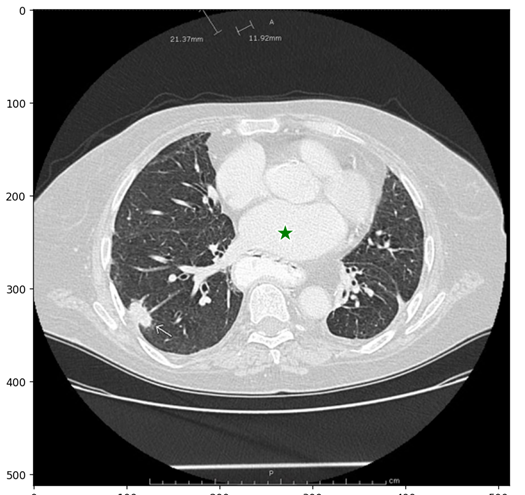

医学图像:

该图片是测试图片,从网站上下载的。

在图片上,选择一个点。点的输入格式为(x, y)和并表示出点所带有的标签1(前景点)或0(背景点)。可以输入多个点,在这里我们先只用一个点,选择的点会显示为一个五角星的标记。